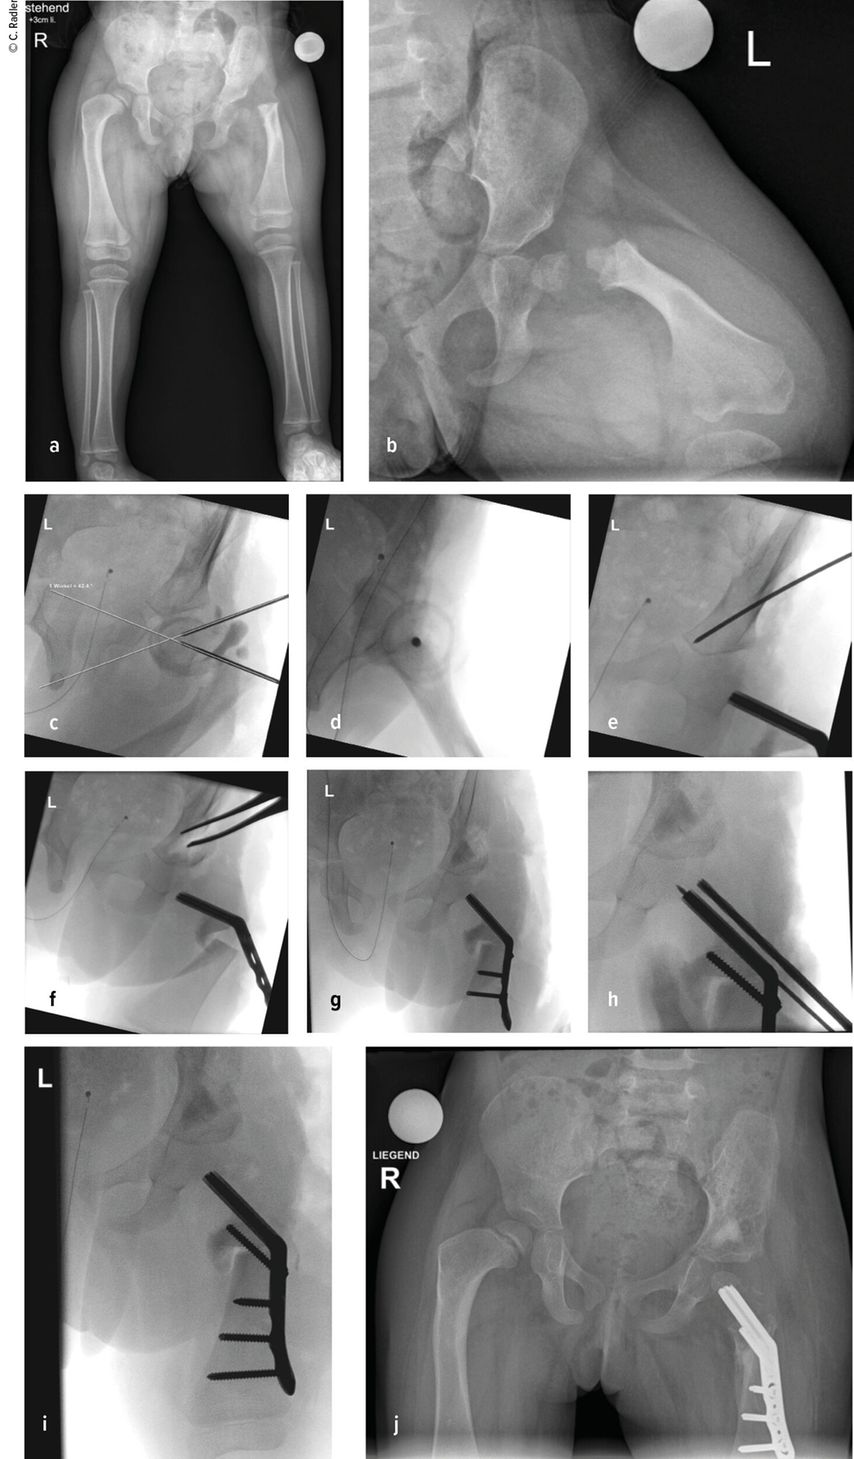

Milde Formen – Typ 1A – zeigen oft nur einen leichten Schenkelhalsvarus und eine verminderte femorale Antetorsion beziehungsweise Retroversion zusätzlich zur Verkürzung. Oft zeigt sich bei diesem Typ auch eine milde subtrochantäre Varusstellung und Sklerose. Mit zunehmendem Schweregrad addiert sich eine azetabuläre Dysplasie, wobei besonders die obere und hintere Überdachung der Hüfte vermindert ist. Beim Typ 1A ist in seltenen Fällen keine vorbereitende Operation erforderlich, insbesondere wenn die Überdachung der Hüfte sehr gut ist und ein CE-Winkel von über 20 Grad vorliegt. Es kann dann direkt mit einer Verlängerung des Femurs begonnen werden. Je nach verwendeter OP-Technik können eine eventuell vorhandene Retroversion und Varusstellung im Rahmen der Verlängerungsoperation akut über eine zusätzliche proximale Osteotomie und Montage an den oberen Teil des Fixateurs adressiert werden. (Abb.1).

Abb. 1: Operative Versorgung eines CFD rechts mit Varusstellung an der Hüfte und subtrochantärer Sklerosierung

In allen Fällen, in denen eine – wenn auch nur grenzwertige – Dysplasie des Acetabulums vorliegt, ist vor einer Verlängerung eine Beckenosteotomie (Acetabuloplastik) erforderlich.

Im Rahmen dieser Operation können auch die Retrotorsion und der Schenkelhalsvarus korrigiert werden. Eine Verlängerung bei nicht optimal überdachter Hüfte führt meist zu einer Subluxation oder Luxation, was eine schwerwiegende Komplikation darstellt, die nur schwer und meist nicht folgenlos zu beheben ist. Auch bei älteren Patienten ist die Überdachung vor einer eventuellen Verlängerung zu überprüfen, wobei besonders ab dem 4. Lebensjahr eine Tripelosteotomie eine bessere Überdachung und Einstellung der Pfanne gegenüber einer Acetabuloplastik erlaubt (Abb.2).

Abb. 2:Versorgung eines kurzen Pfannendachs mittels Tripelosteotomie, um die Hüfte während der Verlängerung vor (Sub-)Luxation zu schützen

Der Typ 1B ist durch eine verzögerte Ossifikation/Pseudoarthrose subtrochantär oder im Schenkelhalsbereich charakterisiert, wobei auch ein kombinierter Typ mit Schenkelhals und subtrochantär verzögerter Ossifikation vorliegen kann. Klinisch imponiert neben der massiven Verkürzung die Außenrotations- und Beugekontraktur. In diesen Fällen ist eine komplexe Rekonstruktion, bestehend aus mehreren Schritten, erforderlich, die als Super-Hip-Operation subsumiert wird (Abb. 3).